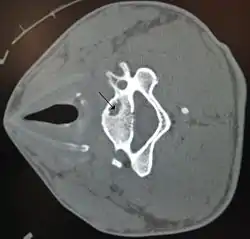

![]() A bone cyst in the vertebra of the neck as seen on CT A bone cyst in the vertebra of the neck as seen on CT | |